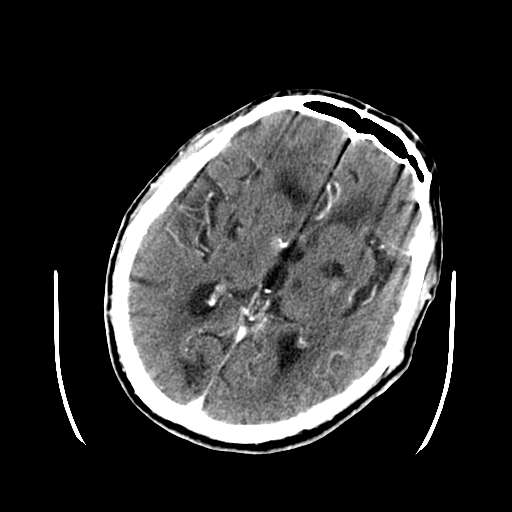

考虑:颅底脑膜瘤。双侧基底节区脑腔隙性脑软化灶。脑萎缩。脑白质变性。

此患者10天后又行ct平扫,病灶内部密度下降,整理后发布于:

http://www.radida.com/radinet/read.php?tid=31856